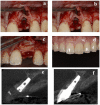

Resorbable Membrane Pouch Technique for Single-Implant Placement in the Esthetic Zone: A Preliminary Technical Case Report

The conventional protocol for lateral guided bone regeneration (GBR) in esthetic areas requires the securing of resorbable collagen membranes using titanium cortical bone pins to immobilize bone grafts. These procedures are highly invasive and can increase patient morbidity and discomfort. Herein, we introduce a minimally invasive novel resorbable membrane pouch technique, wherein collagen membranes can be immobilized by securing them to the periosteum without the need of titanium pins. We describe 11 cases of single-immediate- or delayed-implant placement in the atrophic maxilla esthetic zone. All implants were successful and functional without pain or inflammation and with optimal soft-tissue health and esthetics. Radiographic evaluation with cone-beam computed tomography (CBCT) and esthetic assessment using the pink esthetic score (PES) were performed. At the time of implant placement, the average augmented bone width was 2.8 ± 0.6 mm on CBCT analysis. In all cases, resorption of the augmented bone was confirmed with an average of -1.3 ± 0.8 mm. Soft-tissue outcomes were scored 1 year after permanent restoration. The PES score 1 year after treatment was 11.9 ± 1.4. The resorbable membrane pouch technique with immediate or delayed implant placement for buccal dehiscence in the esthetic area can be predictable and is minimally invasive.